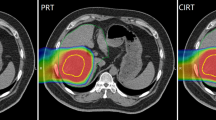

Representative dose distributions of SBRT and C-ion RT are shown in Figs. 1 and 2. Dosimetric parameters of C-ion RT and SBRT were calculated from both treatment plans and summarized in Table 1. The PTV D90 was 59.6 ± 0.2 Gy(RBE) for C-ion RT, as compared to 56.6 ± 0.3 Gy for SBRT, indicating a significant difference (p < 0.05). The HI and CI were 1.19 ± 0.03 and 0.79 ± 0.06, respectively, for C-ion RT, as compared to 1.21 ± 0.01 and 0.37 ± 0.02, respectively, for SBRT; only CI showed a significant difference. MLD for normal tissue sparing was 8.1 ± 1.4 Gy(RBE) for C-ion RT, as compared to 16.1 ± 2.5 Gy for SBRT (p < 0.05). The relationship between MLD and GTV diameter is shown in Fig. 3. V5 to V50 were higher in SBRT than C-ion RT, while significant differences were observed for V5, V10, and V20. Dmax of the GI tract was higher in SBRT than C-ion RT, but did not constitute a significant difference.